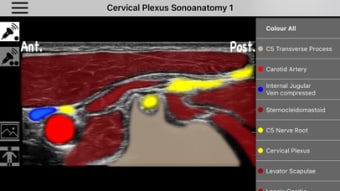

AnSo Anestesia Sonoanatomía es una aplicación para iPhone que proporciona una comprensión integral de la sonoanatomía relevante para el anestesista. Con más de 250 imágenes de ultrasonido y 1500 superposiciones de color de sonoanatomía, esta aplicación es un recurso conveniente diseñado para ayudar a los anestesistas a identificar la sonoanatomía común de manera eficiente en el tiempo dentro del ajetreado quirófano. Creado por anestesistas en ejercicio con interés en la enseñanza de la ecografía y la anestesia regional, AnSo proporciona múltiples ejemplos de la sonoanatomía ya que cada individuo es diferente.